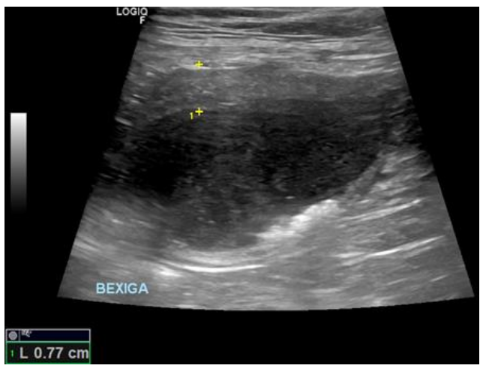

Após detecção de obstrução uretral e múltiplas cistolitíases, foi realizado procedimento de cistocentese para alívio imediato, seguido da implantação de cateter uretral. Com base nos achados da ultrassonografia transoperatória e da uretrocistografia retrógrada, diagnosticou-se ruptura parcial de uretra prostática com presença de cálculo migrado da bexiga para o interior da próstata.

Com auxílio da ultrassonografia transoperatória, foi identificado que os cálculos haviam migrado ao interior da lesão prostática, portanto, foi realizado tentativa de hidropulsão através do catéter uretral na tentativa de retorná-los à vesícula urinária, mas sem sucesso com a técnica. O paciente foi então encaminhado para a realização de exame de Uretrocistografia Retrógrada, para confirmar a suspeita levantada de ruptura de uretra em sua porção prostática.

Após os 7 dias, foi realizada a última radiografia contrastada, que não evidenciou sinais de extravasamento de contraste e confirmou a cicatrização do ponto de ruptura.

O caso descrito demonstra que a ruptura parcial de uretra prostática em cães, embora rara, deve ser considerada em pacientes com histórico de urolitíase e sinais de obstrução urinária grave. O diagnóstico precoce por meio de exames contrastados e ultrassonografia transoperatória mostrou-se essencial para a definição da conduta terapêutica.